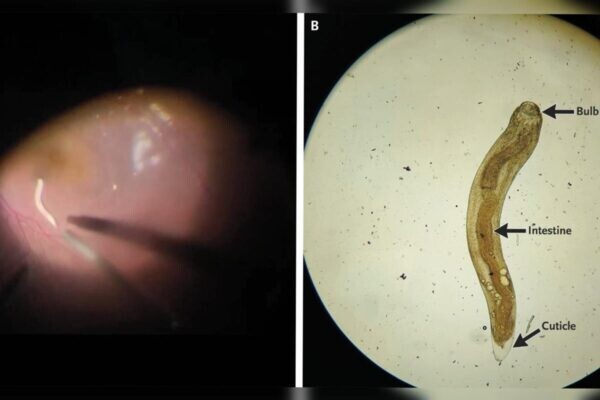

O globo ocular estava avermelhado, a pupila dilatada e fixa, e a precisão visual havia caído para 20/80. Durante o exame detalhado, os médicos identificaram o parasita se movendo no chamado “segmento posterior” — a parte interna e mais profunda do olho.

Para salvar a visão do paciente, foi realizada uma cirurgia chamada vitrectomia pars plana, que retira o humor vítreo (substância gelatinosa dentro do olho) e permitiu a retirada do verme.

Após o procedimento, o homem recebeu tratamento com glicocorticoides orais e oculares, apresentando melhora dos sintomas após oito semanas. Mesmo assim, o desenvolvimento de catarata limitou a recuperação da visão a 20/40. O que é a gnatostomíase ocular? É uma doença parasitária causada pela infecção do verme pertencente ao gênero Gnathostoma. É rara em humanos, porém, mais frequente em regiões da Ásia, Tailândia e México, onde o consumo de alimentos crus ou mal cozidos é comum. A infecção pelo parasita ocorre pela ingestão de larvas presentes em carnes contaminadas , como peixe, frango, répteis ou anfíbios, principalmente quando servidos crus. Em casos raros, as larvas conseguem migrar para o olho , causando inflamação intensa e danos à visão. Os principais sintomas são visão embaçada, vermelhidão, dor ocular e, em alguns casos, percepção de movimento dentro do olho . Mesmo após a retirada, podem surgir complicações, como catarata e perda parcial da visão . A gnatostomíase é considerada uma zoonose — doença transmitida de animais para humanos. Apesar de rara, chama atenção pela gravidade quando afeta o sistema nervoso ou os olhos. O caso indiano reforça o alerta para os riscos de consumir carnes e peixes crus em regiões onde o parasita circula.